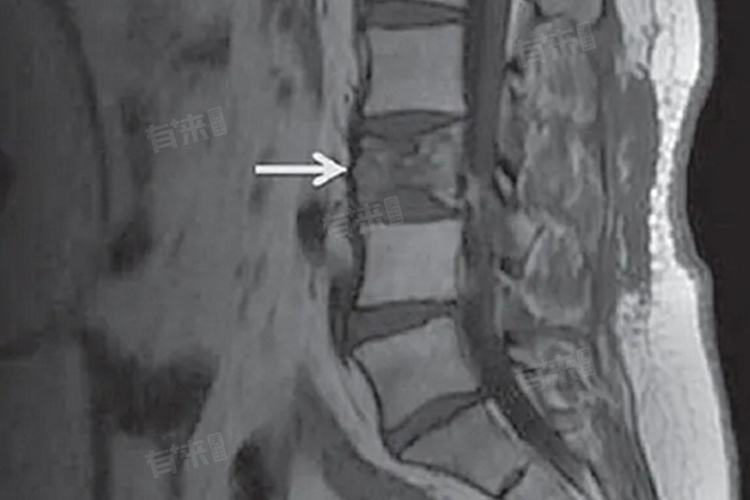

- 骨质破坏:骨转移导致骨质破坏,可能引发病理性骨折,常发生在承重骨如脊柱、股骨等部位,不仅增加患者的痛苦,还可能导致严重的并发症如截瘫、大小便失禁等。对于乳腺癌术后患者,应定期进行骨骼检查,及时发现并处理骨质破坏情况。

- 早期筛查与诊断:乳腺癌患者应定期进行骨骼扫描等检查,以便及时发现骨转移病灶。对于疑似骨转移的患者,应进一步进行CT、MRI等影像学检查以明确诊断。骨放射性核素扫描作为初筛诊断方法,具有灵敏度高、早期发现的优点,但应结合其他检查以提高诊断准确性。